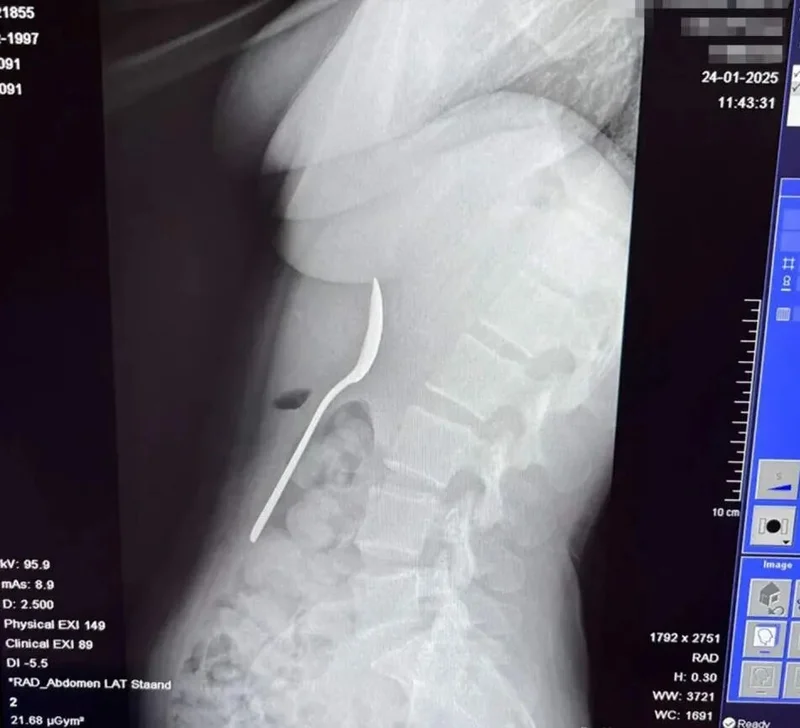

“我的同事们都不相信我,直到我给他们看了X光片!我没有经历什么永久性损伤,不过,我得永远背着‘勺子女’的名声了。”

终于,等了两天,她在局麻下取出了勺子。

因为只是局麻,Amelinckx仍能感觉到勺子被取出的过程,感到它穿过食道、喉咙......

“他们把东西拉出来的时候,不让我吞咽。它们不得不把它在我胃里旋转,导致了少量胃出血。这个过程并不愉快,但取出来的时候,我感觉一块石头终于落地了。我很开心最后不必开刀,只用胃镜就能解决。”